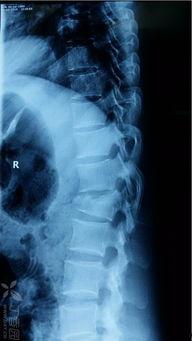

首先,我们要了解一下什么是脊柱骨折。脊柱骨折,顾名思义,就是脊椎骨发生了断裂。这种情况可能是由外力撞击、跌倒、扭伤等原因引起的。听起来是不是很严重?没错,脊柱骨折确实会给患者带来很大的痛苦。